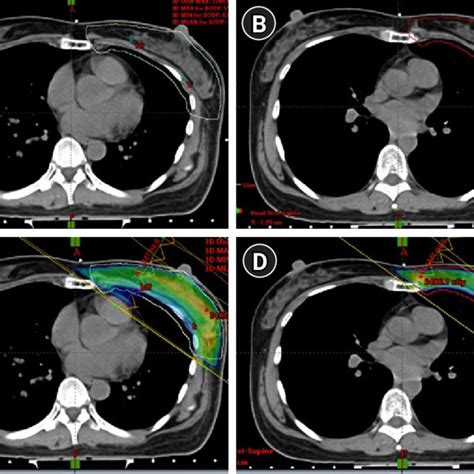

researchgate.net

Computed tomography (CT) simulation and treatment plan…